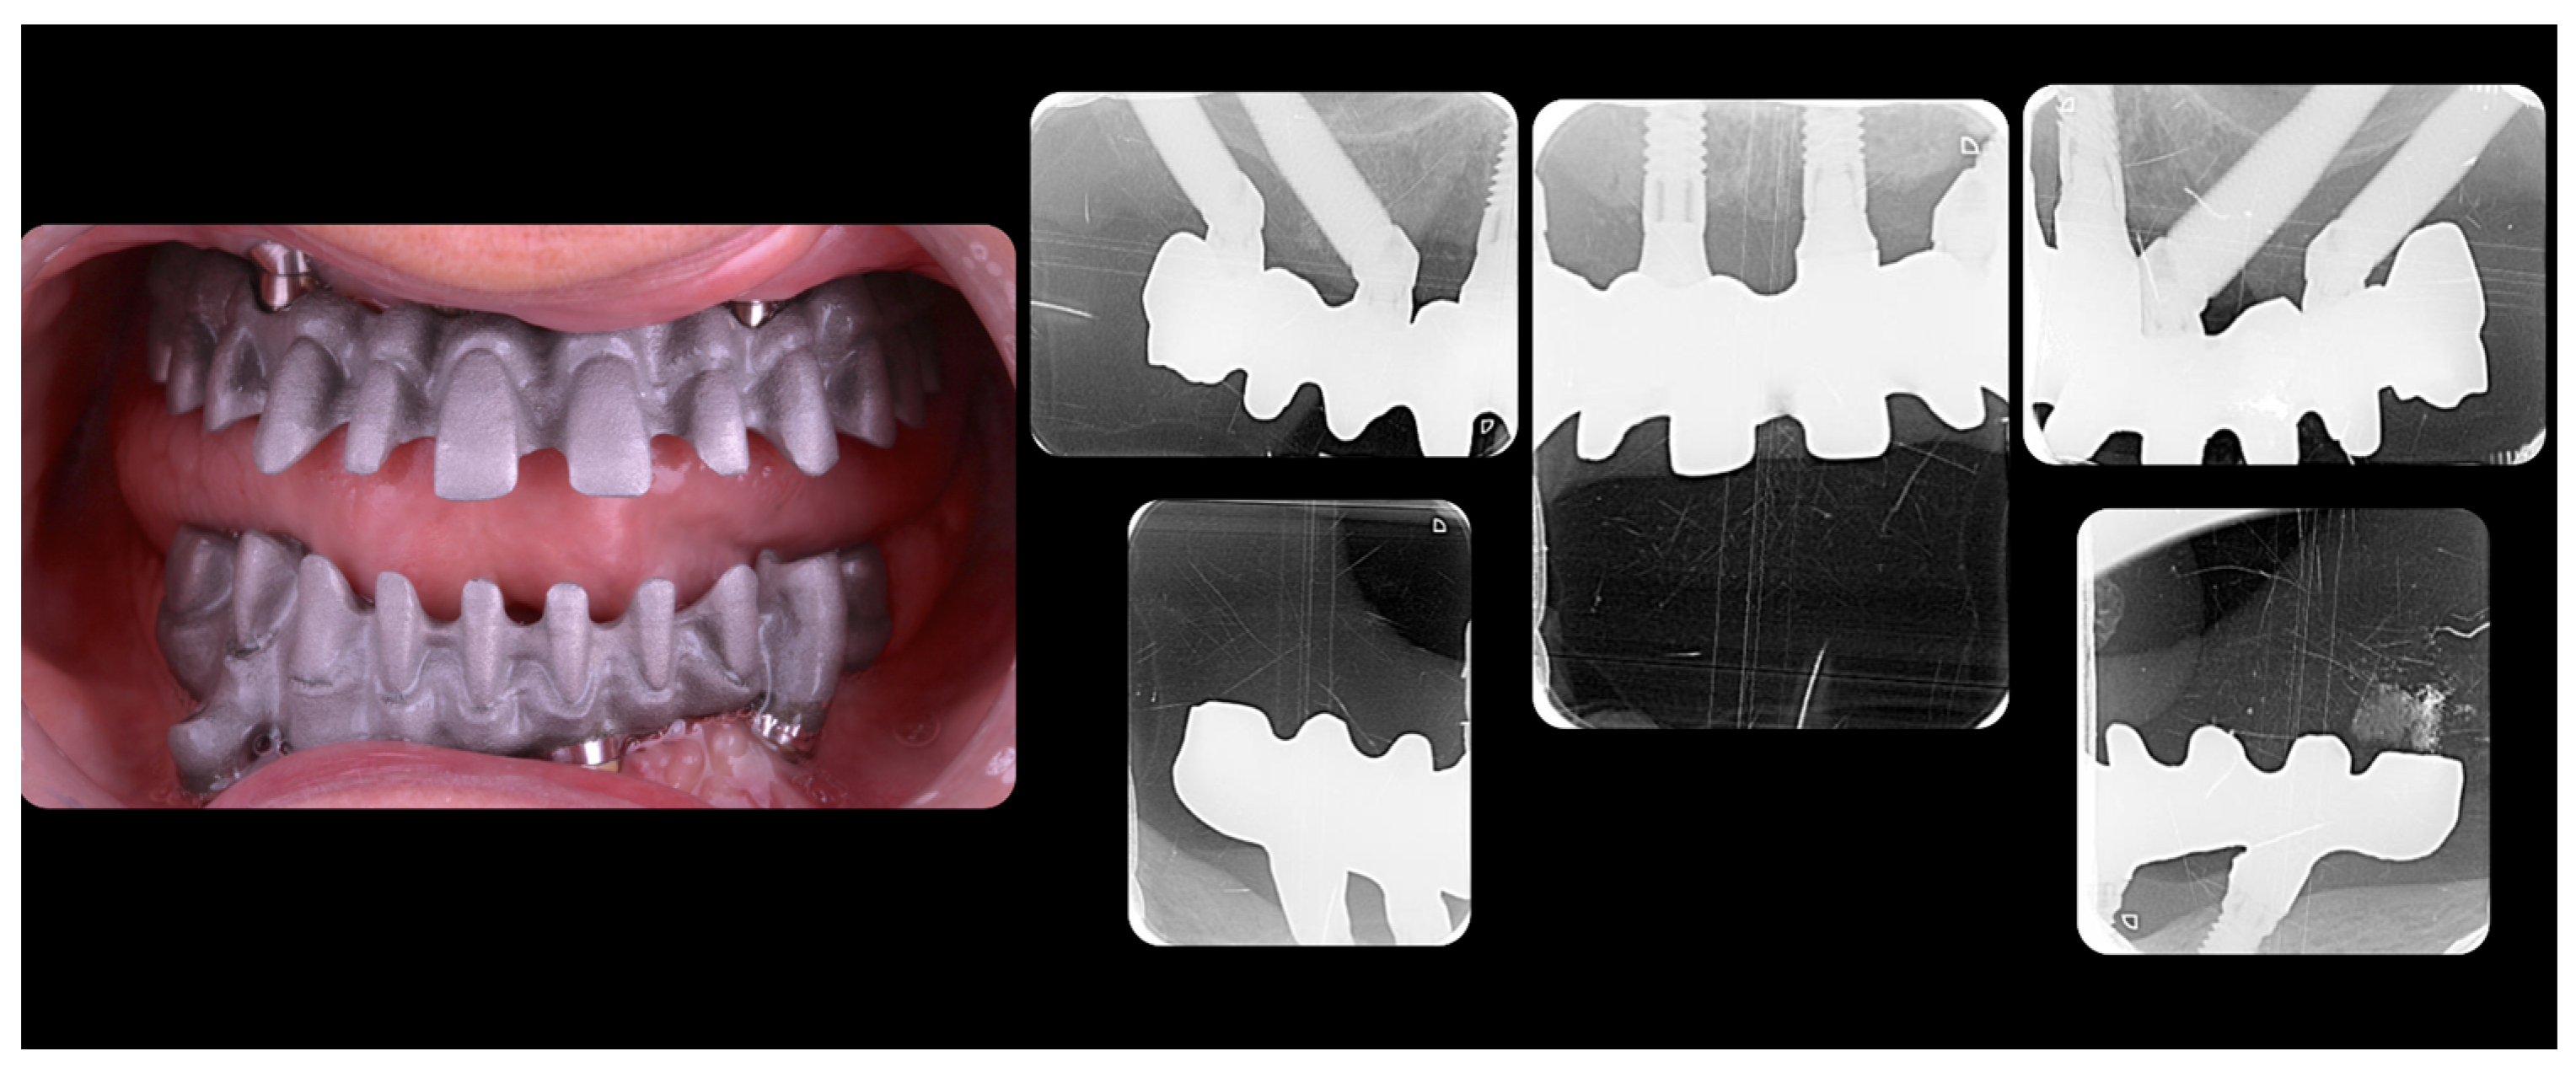

2. Material and Methods